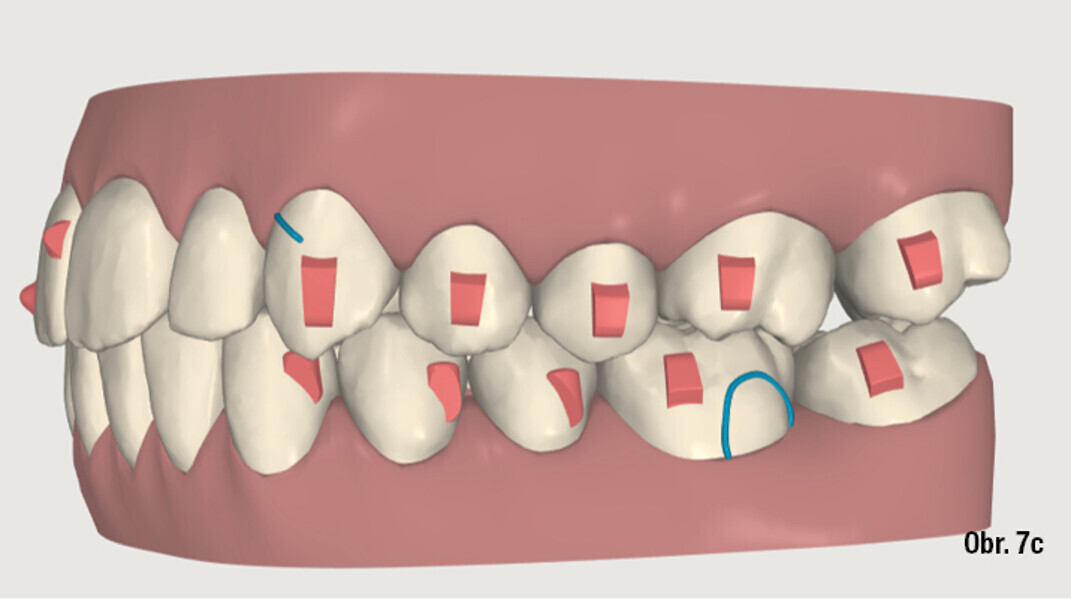

Distalizace horních molárů pomocí alignerů a cyklických sil